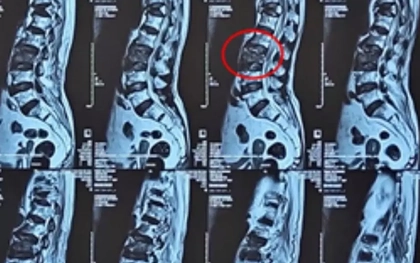

Bơm ‘xi măng’ vào đốt sống cứu cụ bà 100 tuổi

Ở tuổi 100, cơn đau lưng dữ dội do gãy xẹp đốt sống đã khiến cụ bà gần như bất động. Các bác sĩ đã thực hiện phương pháp bơm xi măng vào đốt sống giúp cụ thoát khỏi đau đớn, phục hồi vận động.